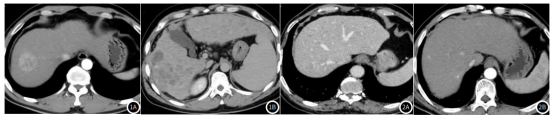

图1A-图1B. 肝细胞肝癌MSCT图像;

图1A. 病灶呈均匀强化,可见等密度的假包膜;图1B:动脉期肝细胞肝癌周边出现明显强化效应。

图2A-图2B. 肝硬化结节MSCT图像;

图2A. 肝包膜边沿不光整,肝裂增宽;图2B:肝脏表面平滑,呈现多发小结节。